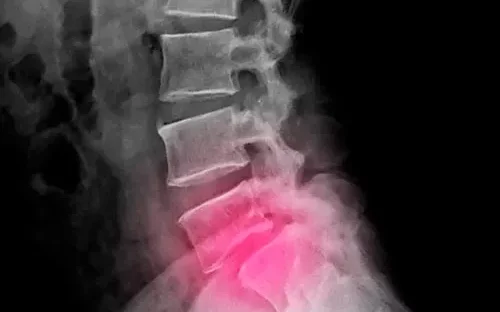

La espondilolistesis es una enfermedad en la que los huesos de la espina dorsal (vértebras) se deslizan fuera de su lugar y encima de la vértebra inferior. Si se desliza demasiado, el hueso puede presionar el nervio, causando dolor. Normalmente, suele afectar a los huesos de la parte inferior de la espalda.